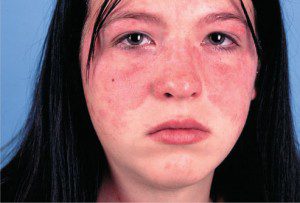

راش پروانه Butterfly Rash

برافروختگی پروانه ای شکل در نواحی مرکزی پوست صورت در اغلب اوقات اولین علامت بیماری “لوپوس سیستمیک” می باشد. ولی همیشه هم این طور نیست زیرا گاهی این علامت پوستی به دلیل بیماری های دیگر مانند روزاسه و یا درماتیت ( اگزما ) تماسی رخ می دهد. به هر حال به اعتقاد پزشکان در صورت بروز این علامت با استفاده از آزمایشات بعدی می توان به تشخیص لوپوس رسید.